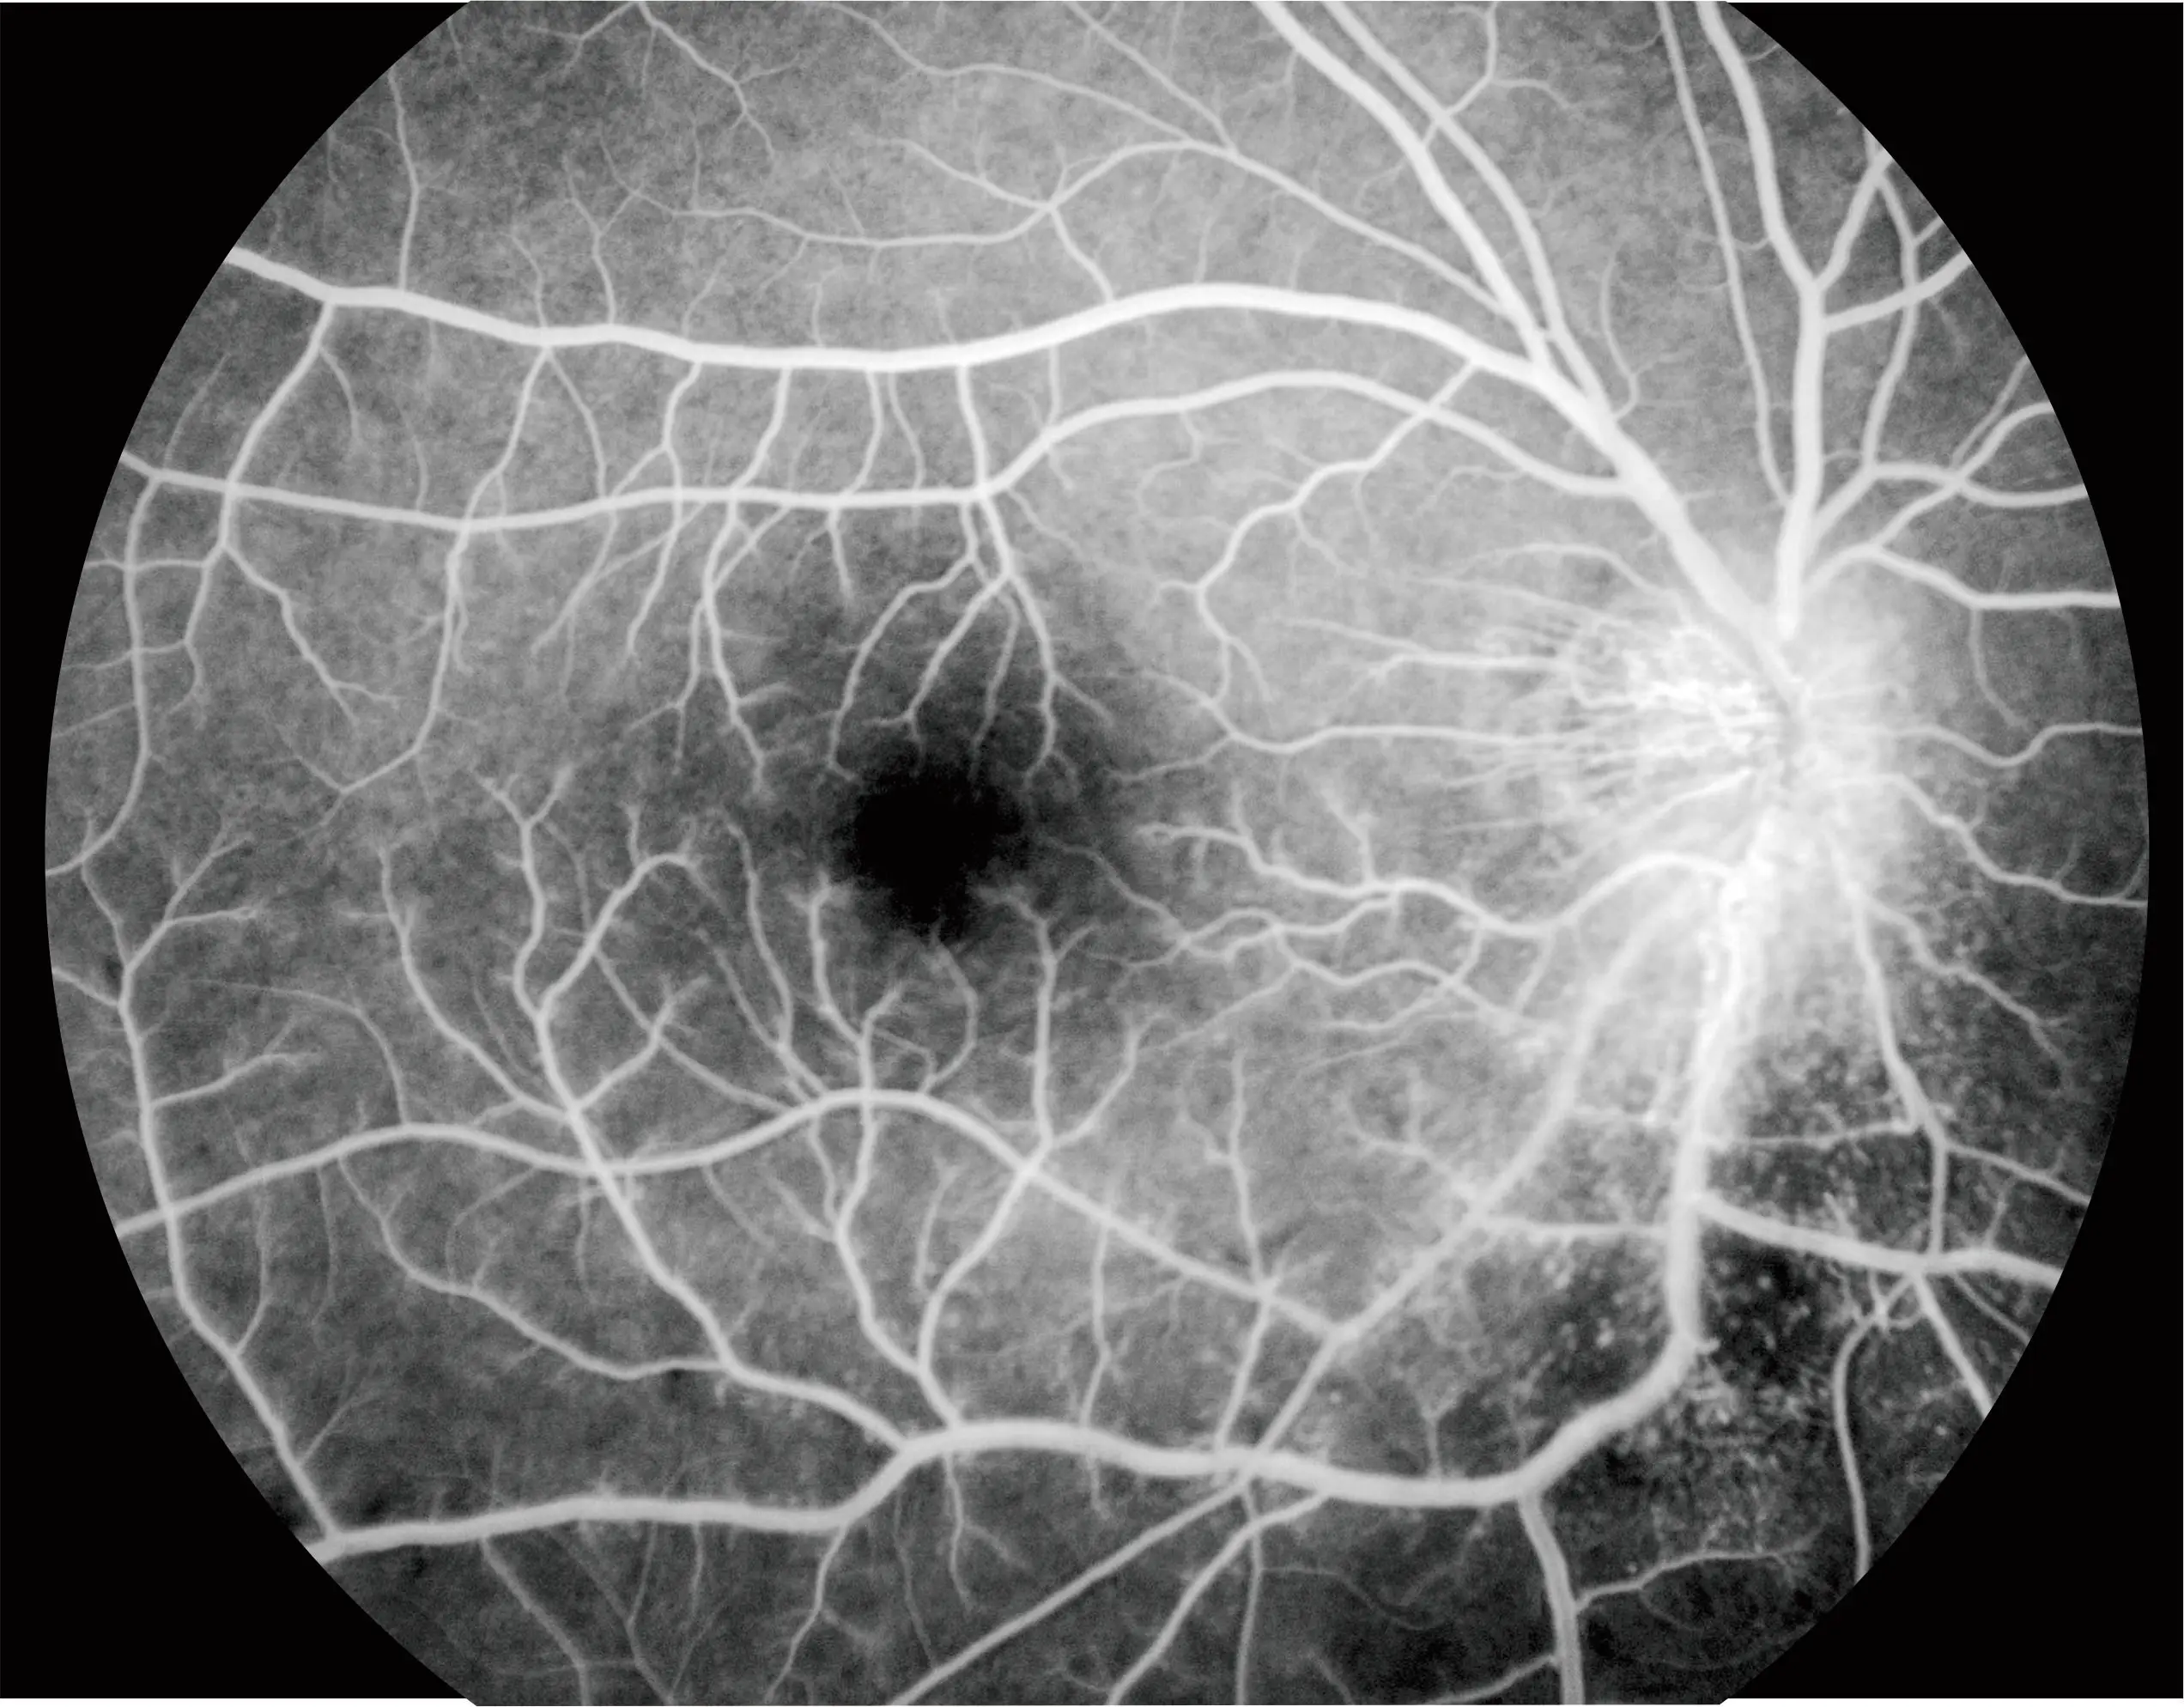

FFA | |||

Red-Free | YES | ||